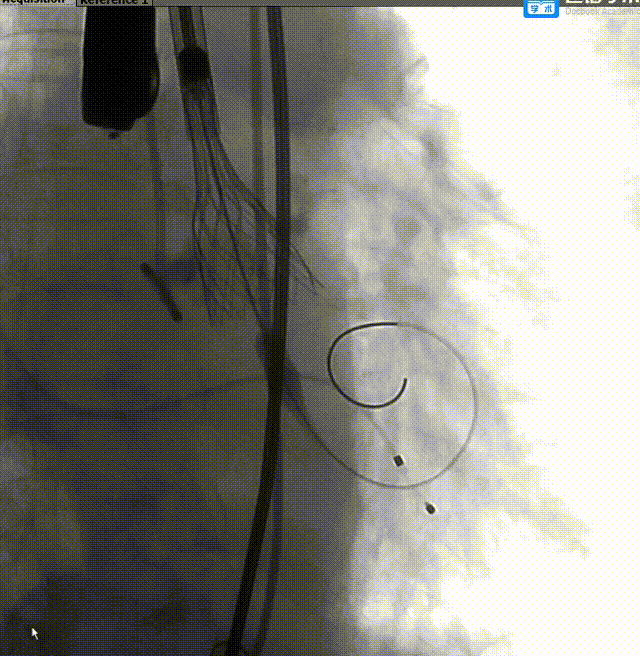

TaurusElite 输送器轻松过弓、跨瓣,TaurusElite AV26精准定位无冠窦最低点。

TaurusElite柔顺过弓

瓣膜定位

起搏150次/分,TaurusElite AV26瓣膜高位快速释放了四分之三,评估冠脉血流良好,无阻挡,瓣膜位置合适,释放后,造影显示反流增加,超声显示瓣周漏主要存在左右钙化嵴处,前向流速明显减小,跨瓣压差由术前60 mmHg减小到20mmHg,瓣膜横截面最大处18mm。

瓣膜工作位评估

术后主动脉根部造影评估

使用22mm球囊后扩,瓣膜展开形态更好。

球囊后扩